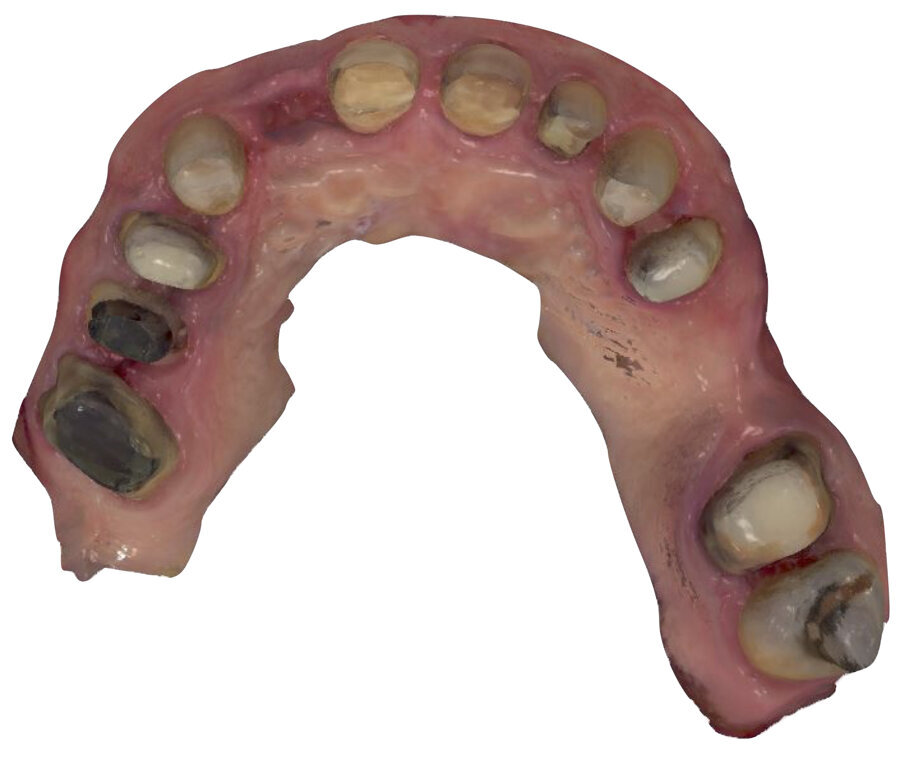

Un paziente di 66 anni, con anamnesi patologica di NIDDM ben compensato e cardio-vasculopatia ischemica in buon compenso farmacologico, si presenta alla nostra attenzione per ascesso parodontale alla radice residua del dente 1.2 e per multiple fratture dei manufatti protesici esistenti (Figg. 1-6). È evidente la presenza di grave malocclusione con perdita di VDO, usure e fratture dei restauri protesici e dei denti residui, presenza di abfractions cervicali. Il paziente evidenzia alla visita modesta dolenzia muscolare alla palpazione, specie a carico dei muscoli pterigoidei mediali e temporali, apertura della bocca ridotta e lieve rumorosità delle TMJ.

L’infezione a carico della radice del dente 1.2 è immediatamente attribuibile a frattura verticale con sondaggio positivo di 9 mm (Fig. 7). Estratta la radice di 1.2 fratturata, il paziente richiede una riabilitazione protesica fissa all’arcata superiore che preveda il minor numero possibile di interventi endodontici e chirurgici. Viene da noi proposta una riabilitazione protesica full arch che consenta, previo studio del caso gnatologico e terapia interlocutoria con provvisori in PMMA, la definizione di un’occlusione a funzione sequenziale in TRP per l’aumento controllato della VDO e la stabilizzazione dei rapporti articolari, ora visibilmente compromessi.